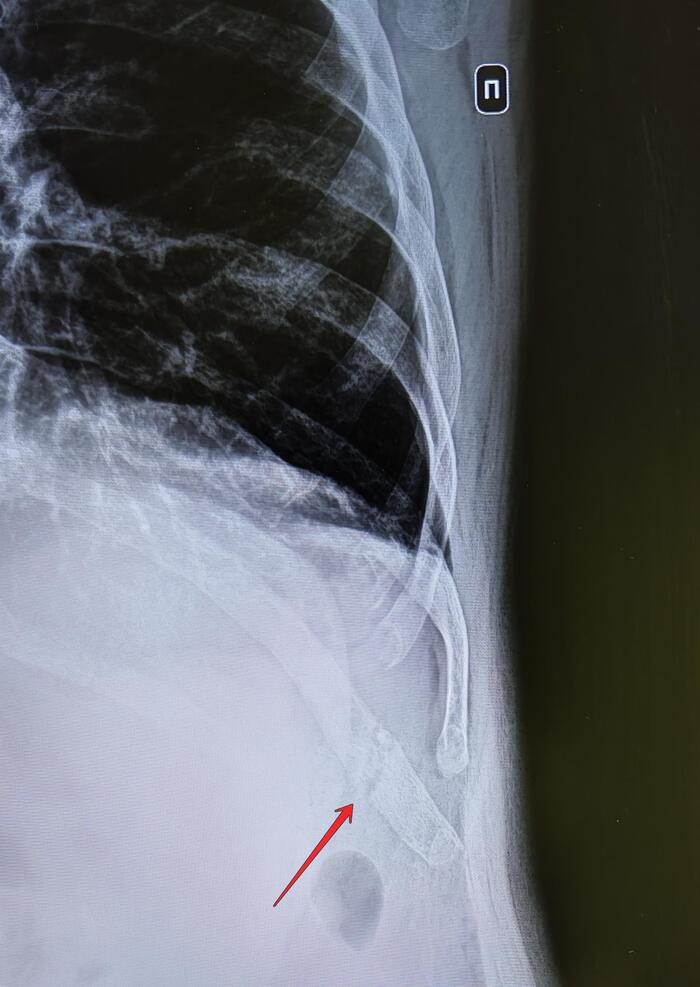

Перелом ребра

Травма(падение на улице) месячной давности.

На Р-граммах левого гемиторакса: по паралопаточной линии визуализируется линия просветления(перелом) костной ткани 10го ребра. Диастаз 2мм.Нарастающая костная мозоль. Заключение: Консолидирующийся перелом 10го ребра слева.

На основании статьи 85 (Временные функциональные расстройства костно-мышечной системы, соединительной ткани, кожи и подкожной клетчатки после лечения болезней, ранений, травм, отравлений и других воздействий внешних факторов)-Г-временно не годен к военной службе сроком на 3 мес.